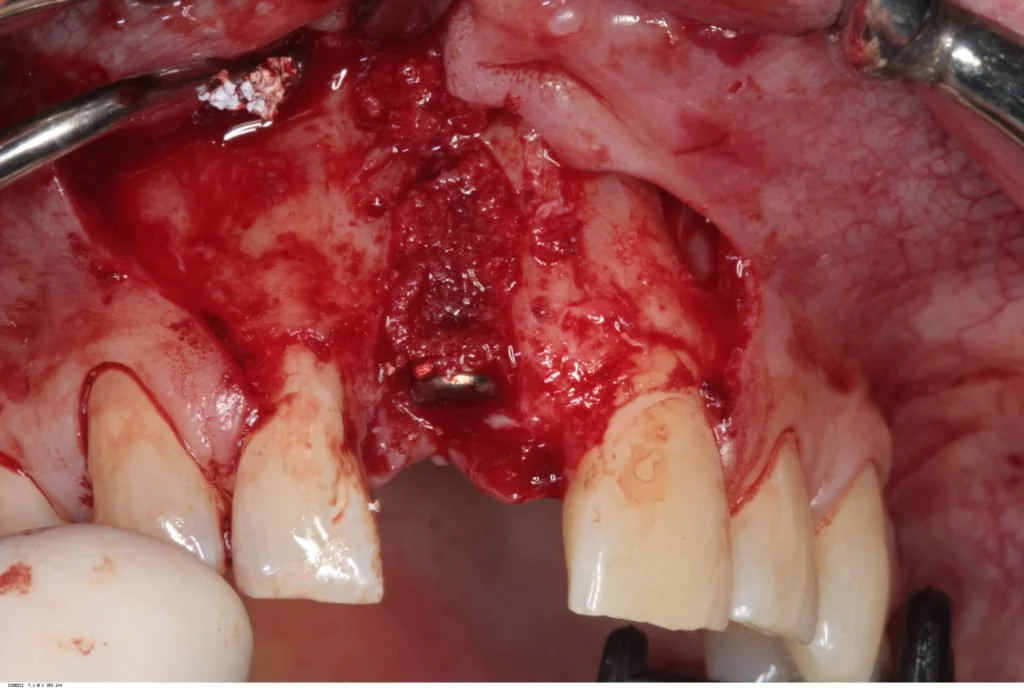

A full thickness flap was raised extending from the distal of 12 to the distal of 21. A Branemark Mark IV implant was placed achieving good primary stability, and the labial plate in the vicinity of the implant perforated to increase blood supply to the planned bone graft.

Autogenous bone chips were then harvested from the local area and placed over the exposed implant threads. This was then protected by a layer of Bioss previously mixed with blood, and then two layers of Bioguide.

The flap was then extended slightly at the relieving incisions, and releasing incisions were made to ensure a completely tension free primary closure. Two mattress sutures (4/0 Vicryl) were used along with multiple interrupted (5/0 Vicryl) sutures.